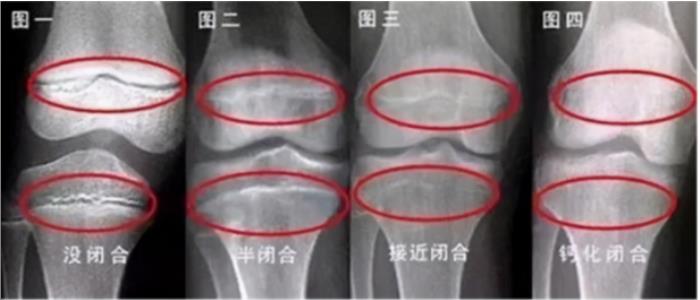

骨骺线是长骨骨干与骨骺之间的一层软骨组织,增长旺盛,能够不断向两侧生成骨细胞,从而使骨骼增长。由于在放射片上类似一条线,而被称为骨骺线。一旦骨骺线出现了闭合现象,就意味着失去了自然长高的潜力。正常情况下,骨骺线会随着年龄的增长而逐渐变薄,骨骺线闭合的时间一般在青春期末尾,但是闭合时间因孩子营养和发育起始时间等因素而存在差异。

1.发育变缓、慢慢长胖

一般孩子的生长是具有一定规律的,进入青春期后每年身高也会增长6-7cm。如果孩子身高在增长速度上出现突然放缓的现象,就说明骨骺线已经进入闭合状态。当身高增长变得缓慢,营养的持续供给会导致孩子出现横向发育,开始长肉变胖。如果开始出现这两种情况,就要多注意了。